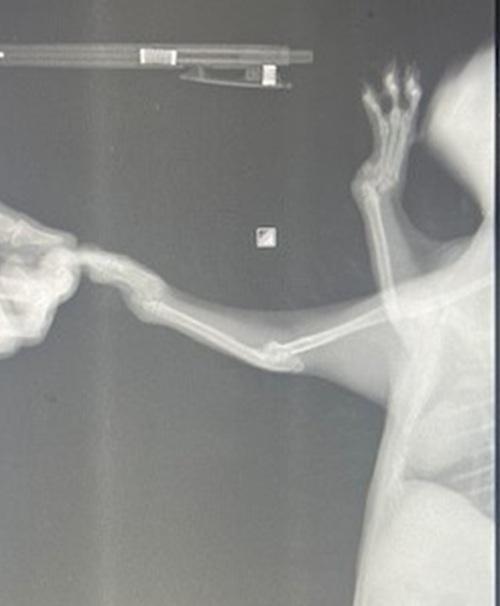

猫種:ナポレオン(ミヌエット)

診断

両前肢手根関節の変形

歩行異常あり

レントゲン検査の結果、両前肢の変形は先天性のものと診断されました。

脱水が認められたため、皮下点滴を行いました。

猫風邪の治療として、点眼薬と抗生剤の投与を開始し、三日間のインターキャット注射を行います。